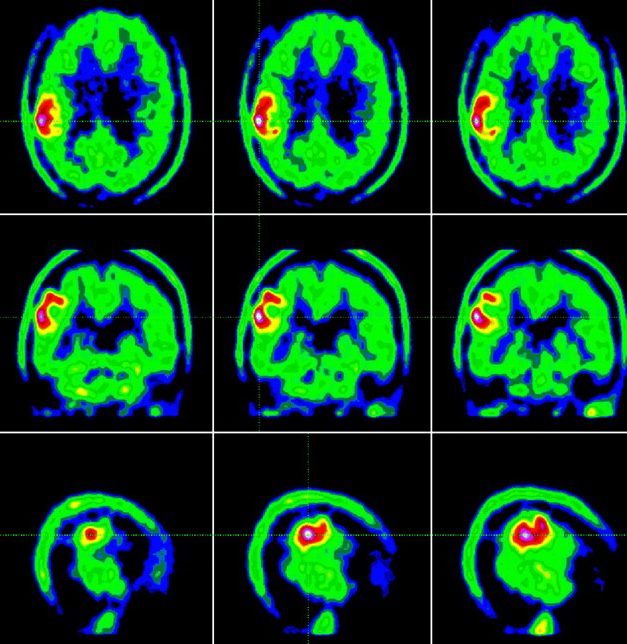

Positron Emission Tomography–Computed Tomography (PET-CT) is an advanced imaging technique that provides unique insight into the biological activity of brain and spinal tumors...